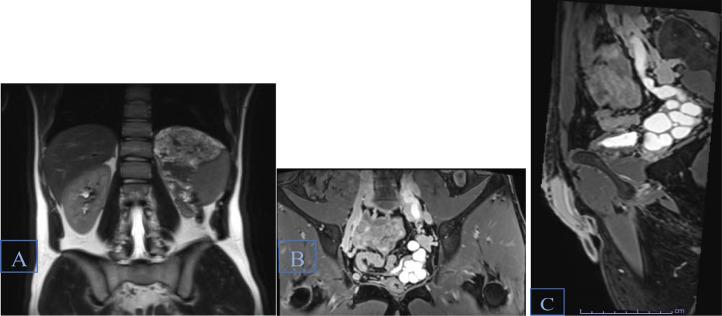

Zinner syndrome comprises a triad of unilateral renal agenesis, ipsilateral seminal vesicle cyst, and ejaculatory duct obstruction, which can be accompanied by additional abnormalities of the genitourinary tract in some cases. Patients may be asymptomatic or present with urinary, reproductive, and/or local pain symptoms. Diagnosis is most commonly achieved via MRI. Here, we present the case of an 18-year-old male previously diagnosed with unilateral renal agenesis, who presented with testicular and penile pain, along with urinary urgency and frequency. MRI of the abdomen and pelvis revealed all three components of Zinner syndrome as well as an ectopic ureter emptying into the seminal vesicle. Our case adds to the existing limited literature on this rare syndrome and broadens the understanding of how this syndrome can present both clinically and radiologically.

齐纳综合征包括单侧肾缺如、同侧精囊囊肿和射精管梗阻三联征,某些情况下可伴有泌尿生殖道的其他异常。患者可能无症状,或出现泌尿系统、生殖系统和/或局部疼痛症状。诊断最常用的方法是磁共振成像(MRI)。在此,我们报告一例18岁男性病例,该患者此前被诊断为单侧肾缺如,现出现睾丸和阴茎疼痛,伴有尿急和尿频。腹部和盆腔的MRI显示了齐纳综合征的所有三个组成部分,以及一条异位输尿管排入精囊。我们的病例补充了关于这种罕见综合征的现有有限文献,并拓宽了对该综合征在临床和影像学上表现的认识。